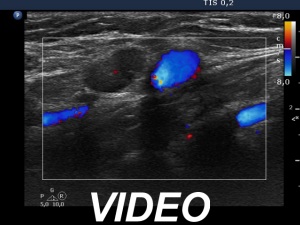

First examination (first, third and fifth rows of images):

Ultrasonography. The thyroid was echonormal and contained multiple inhomogeneous, partly blurred hypoechogenic and moderately hypoechogenic discrete lesions. Multiple lymph nodes were found on both sides of the neck.